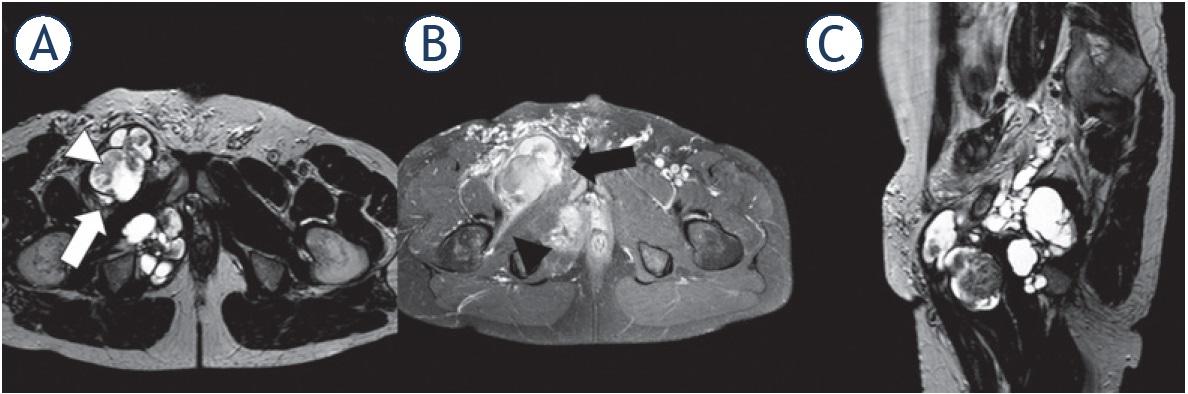

Figure 2